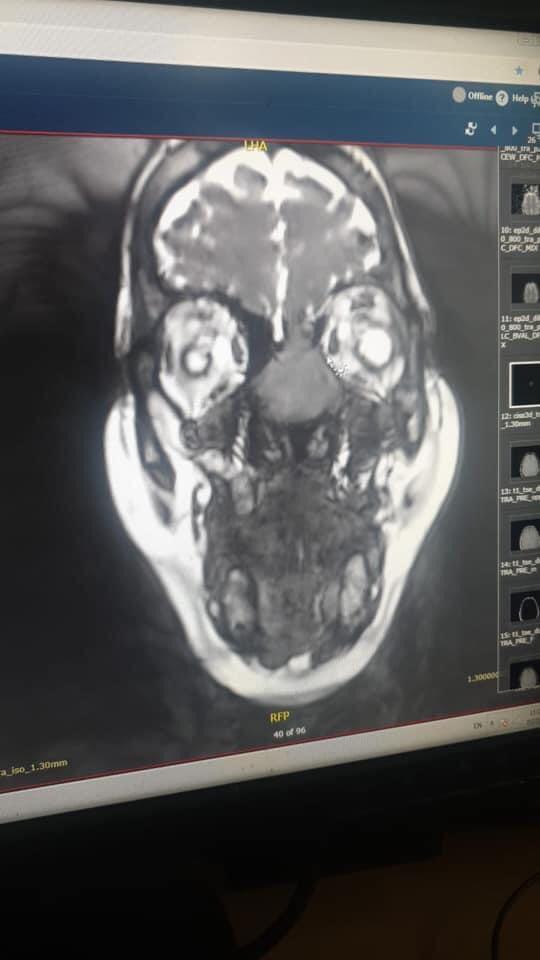

إستئصال ورم خبيث بالأنف لخمسينيه في المدينة الطبية